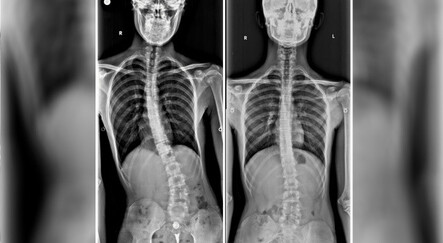

Bel romatizmasının iltihaplı bir romatizma türü olduğunu aktaran Yeşim Çimen “Sakroiliak eklem çoğunlukla ilk olarak etkilenir. Zaman içinde hastalığın ilerlemesi ile tüm omurga tutulumu olabilir. İlerleyen yaşlarda omurgada kemikleşme ve öne eğilme ve bel-boyun hareketlerinde kısıtlılık ortaya çıkar. Erkeklerde kadınlara oranla 2-3 kat fazla görülür. HLA-B 27 geni ile yakın ilişkisi olmakla birlikte tek başına bu genin varlığı hastalık olduğunu göstermez. Hastalık çok sık görülmediği için bel fıtığı ve kireçlenme ile karıştırılarak tanıda gecikmeye neden olabilir” şeklinde konuştu.

Dr. Yeşim Çimen hastalığın belirtileri hakkında şu bilgileri verdi: “En önemli belirti üç aydan uzun süren, istirahatte artan, hareketle azalan bel ağrısıdır. Tipik olarak hasta sabah belde tutukluk ile uyanır. Sabah tutukluğu en az bir saat sıklıkla öğleye kadar devam eder, gün içinde azalır” diyen sözlerine şöyle devam etti: “Dr. Yeşim çimen “Bel ağrısı dışında boyun ağrısı, omuz ağrısı, eklem şişliği, topuk ağrısı, göğüs kafesinde ağrı görülebilir. Gözde kızarıklık ve ağrı, iltihaplı bağırsak hastalıkları, kalp tutulumu eşlik edebilir. Erken dönemde hastalığa bağlı kemik erimesi gelişebilir. Behçet hastalığı ve ailevi Akdeniz ateşi ile birliktelik gösterebilir.”